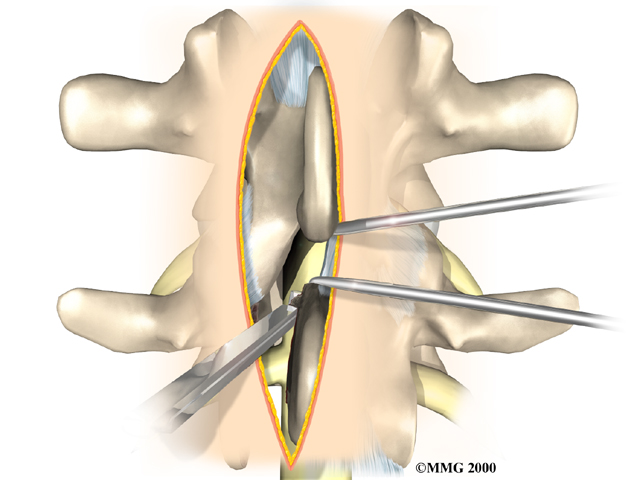

The surgeon first removes any pressure from nearby nerves. This may involve removing part or all of the lamina bone. (The lamina forms the back portion of the bony ring covering the spinal canal.) Then the surgeon takes out any disc fragments and scrapes off nearby bone spurs. In this way, the nerves inside the spinal canal are relieved of additional tension and pressure. The nerve roots are checked to see if they move freely in the spinal canal and as they leave the spine through the small holes between the vertebrae, the neural foramina. If not, the surgeon may cut a larger opening in the neural foramina. This procedure is called foraminotomy.